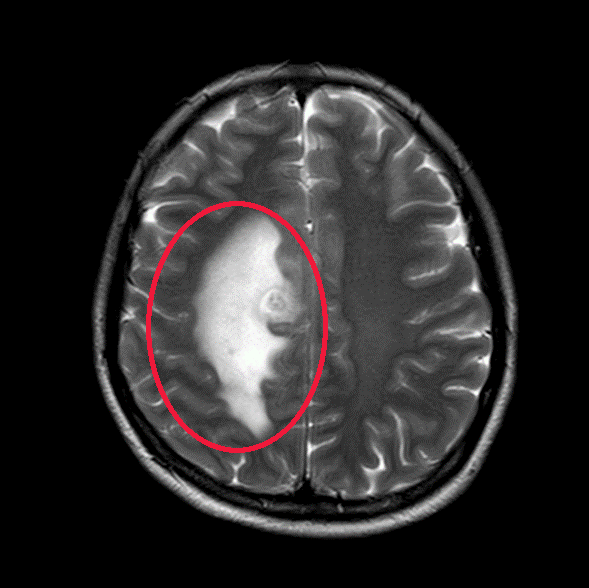

▲治疗前

我们给这位年轻患者口服了靶向药

短短一个月

患者肺部和脑部肿瘤就出现明显退缩